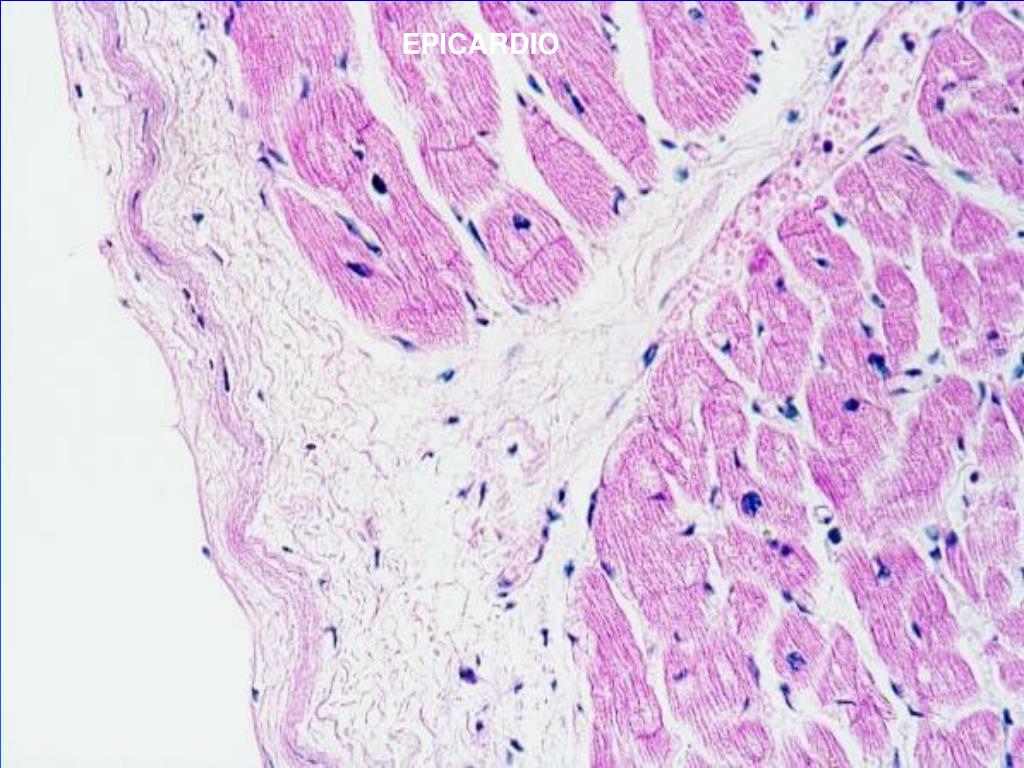

17. CORAZON Pared cardiaca (3 capas) -Epicardio : - capa fibrosa interna de tejido conectivo - capa serosa externa o mesotelio ( capa visceral del pericardio). -Miocardio:formado por varias capas de células musculares estriadas cardíacas de diferente orientación. -Endocardio: formado por un endotelio y un subendotelio que es una fina capa de tejido conectivo laxo.

19. EPICARDIO

20. EPICARDIO